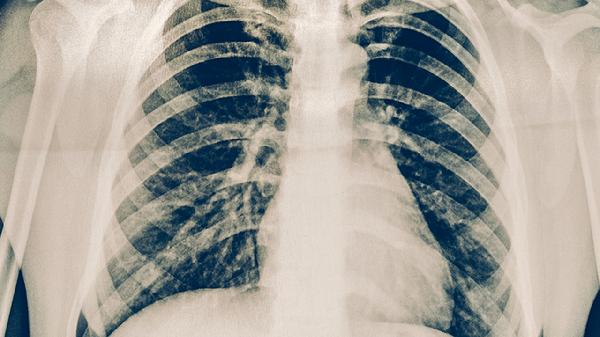

感冒后如出現(xiàn)上述癥狀持續(xù)不緩解,建議及時就醫(yī)進行結(jié)核菌素試驗、胸部X線或CT檢查。確診肺結(jié)核后需嚴格遵醫(yī)囑完成6-9個月的抗結(jié)核治療,避免擅自停藥導(dǎo)致耐藥。日常生活中應(yīng)注意保持室內(nèi)通風(fēng),均衡飲食,適當鍛煉增強免疫力,肺結(jié)核患者咳嗽時應(yīng)掩住口鼻,痰液需消毒處理。